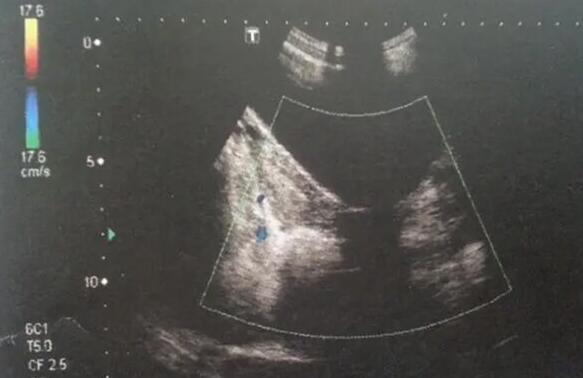

单角子宫和残角子宫是两种妇科疾病,都与子宫形态异常有关。虽然它们都属于子宫发育畸形的一种,但二者在表现、严重程度和治疗方法上存在明显的区别。...